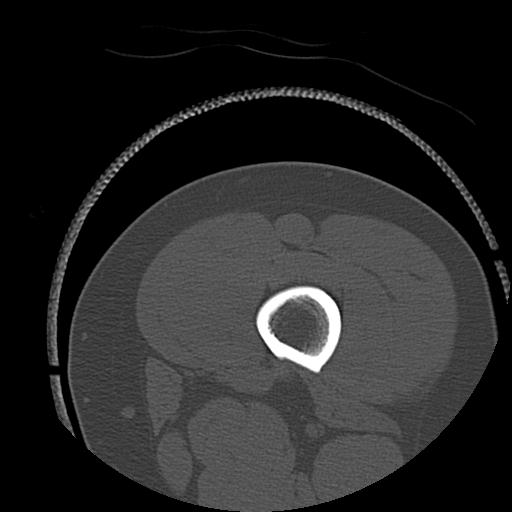

102803 1/12(キウスなし) 1/27 左下腿 4R 30歳女性 左脛骨軸内釘